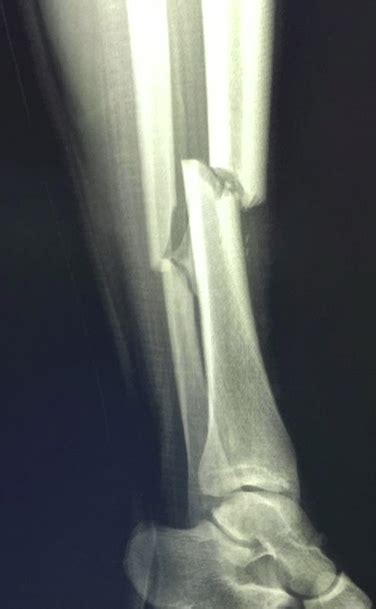

Spiral Fracture: Healing Time, Tibia, and Fibula